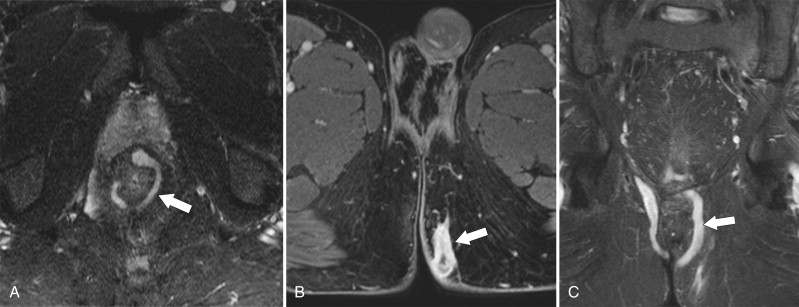

Figure 5-26, Axial ( A and B ) T2-weighted and coronal ( C ) T1-weighted fat-saturated postcontrast MRI in a 43-year-old man with a perianal fistula with an almost circumferential perianal fistula ( arrows ) tracking to the left medial buttock.